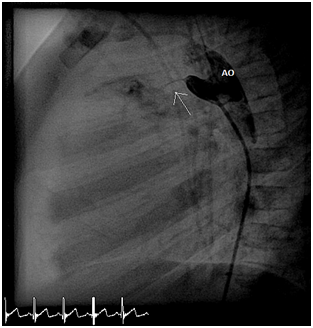

After waiting a few minutes the angiography showed PDA 2mm, with length 9mm (Figure 4).

Figure 4 Angiogram showed the PDA (black arrow).